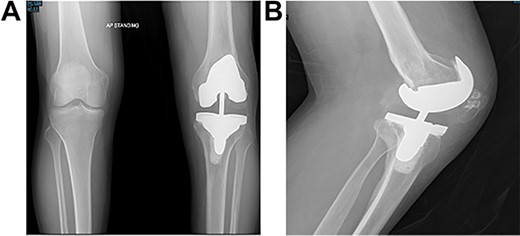

Long weight-bearing knee radiographs showed severe osteoarthritic changes, 18° knee genuvarum and extension deformity of the left distal femur (Fig. 2). Skyline view showed severe arthritic changes (Fig. 3).

Preoperative plain radiographs; (A) severe osteoarthritic changes affecting the left knee with narrowing of the medial knee joint compartment; (B) left femur with dorsal angulation above the condyles and severe patella baja.